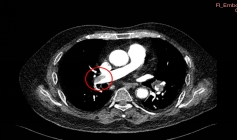

患者杨先生,70岁,因“腰背部疼痛3小时”急诊入院。完善增强CT显示双侧肺动脉主干及分支大面积栓塞,血栓长度超过10cm,右心室明显扩张,肺动脉压力高达60mmHg(正常值<25mmHg)。完善下肢静脉超声证实存在深静脉血栓(DVT)。

左肺动脉上、下叶动脉血栓(术前影像)

肺动脉主干血栓形成(术前影像)